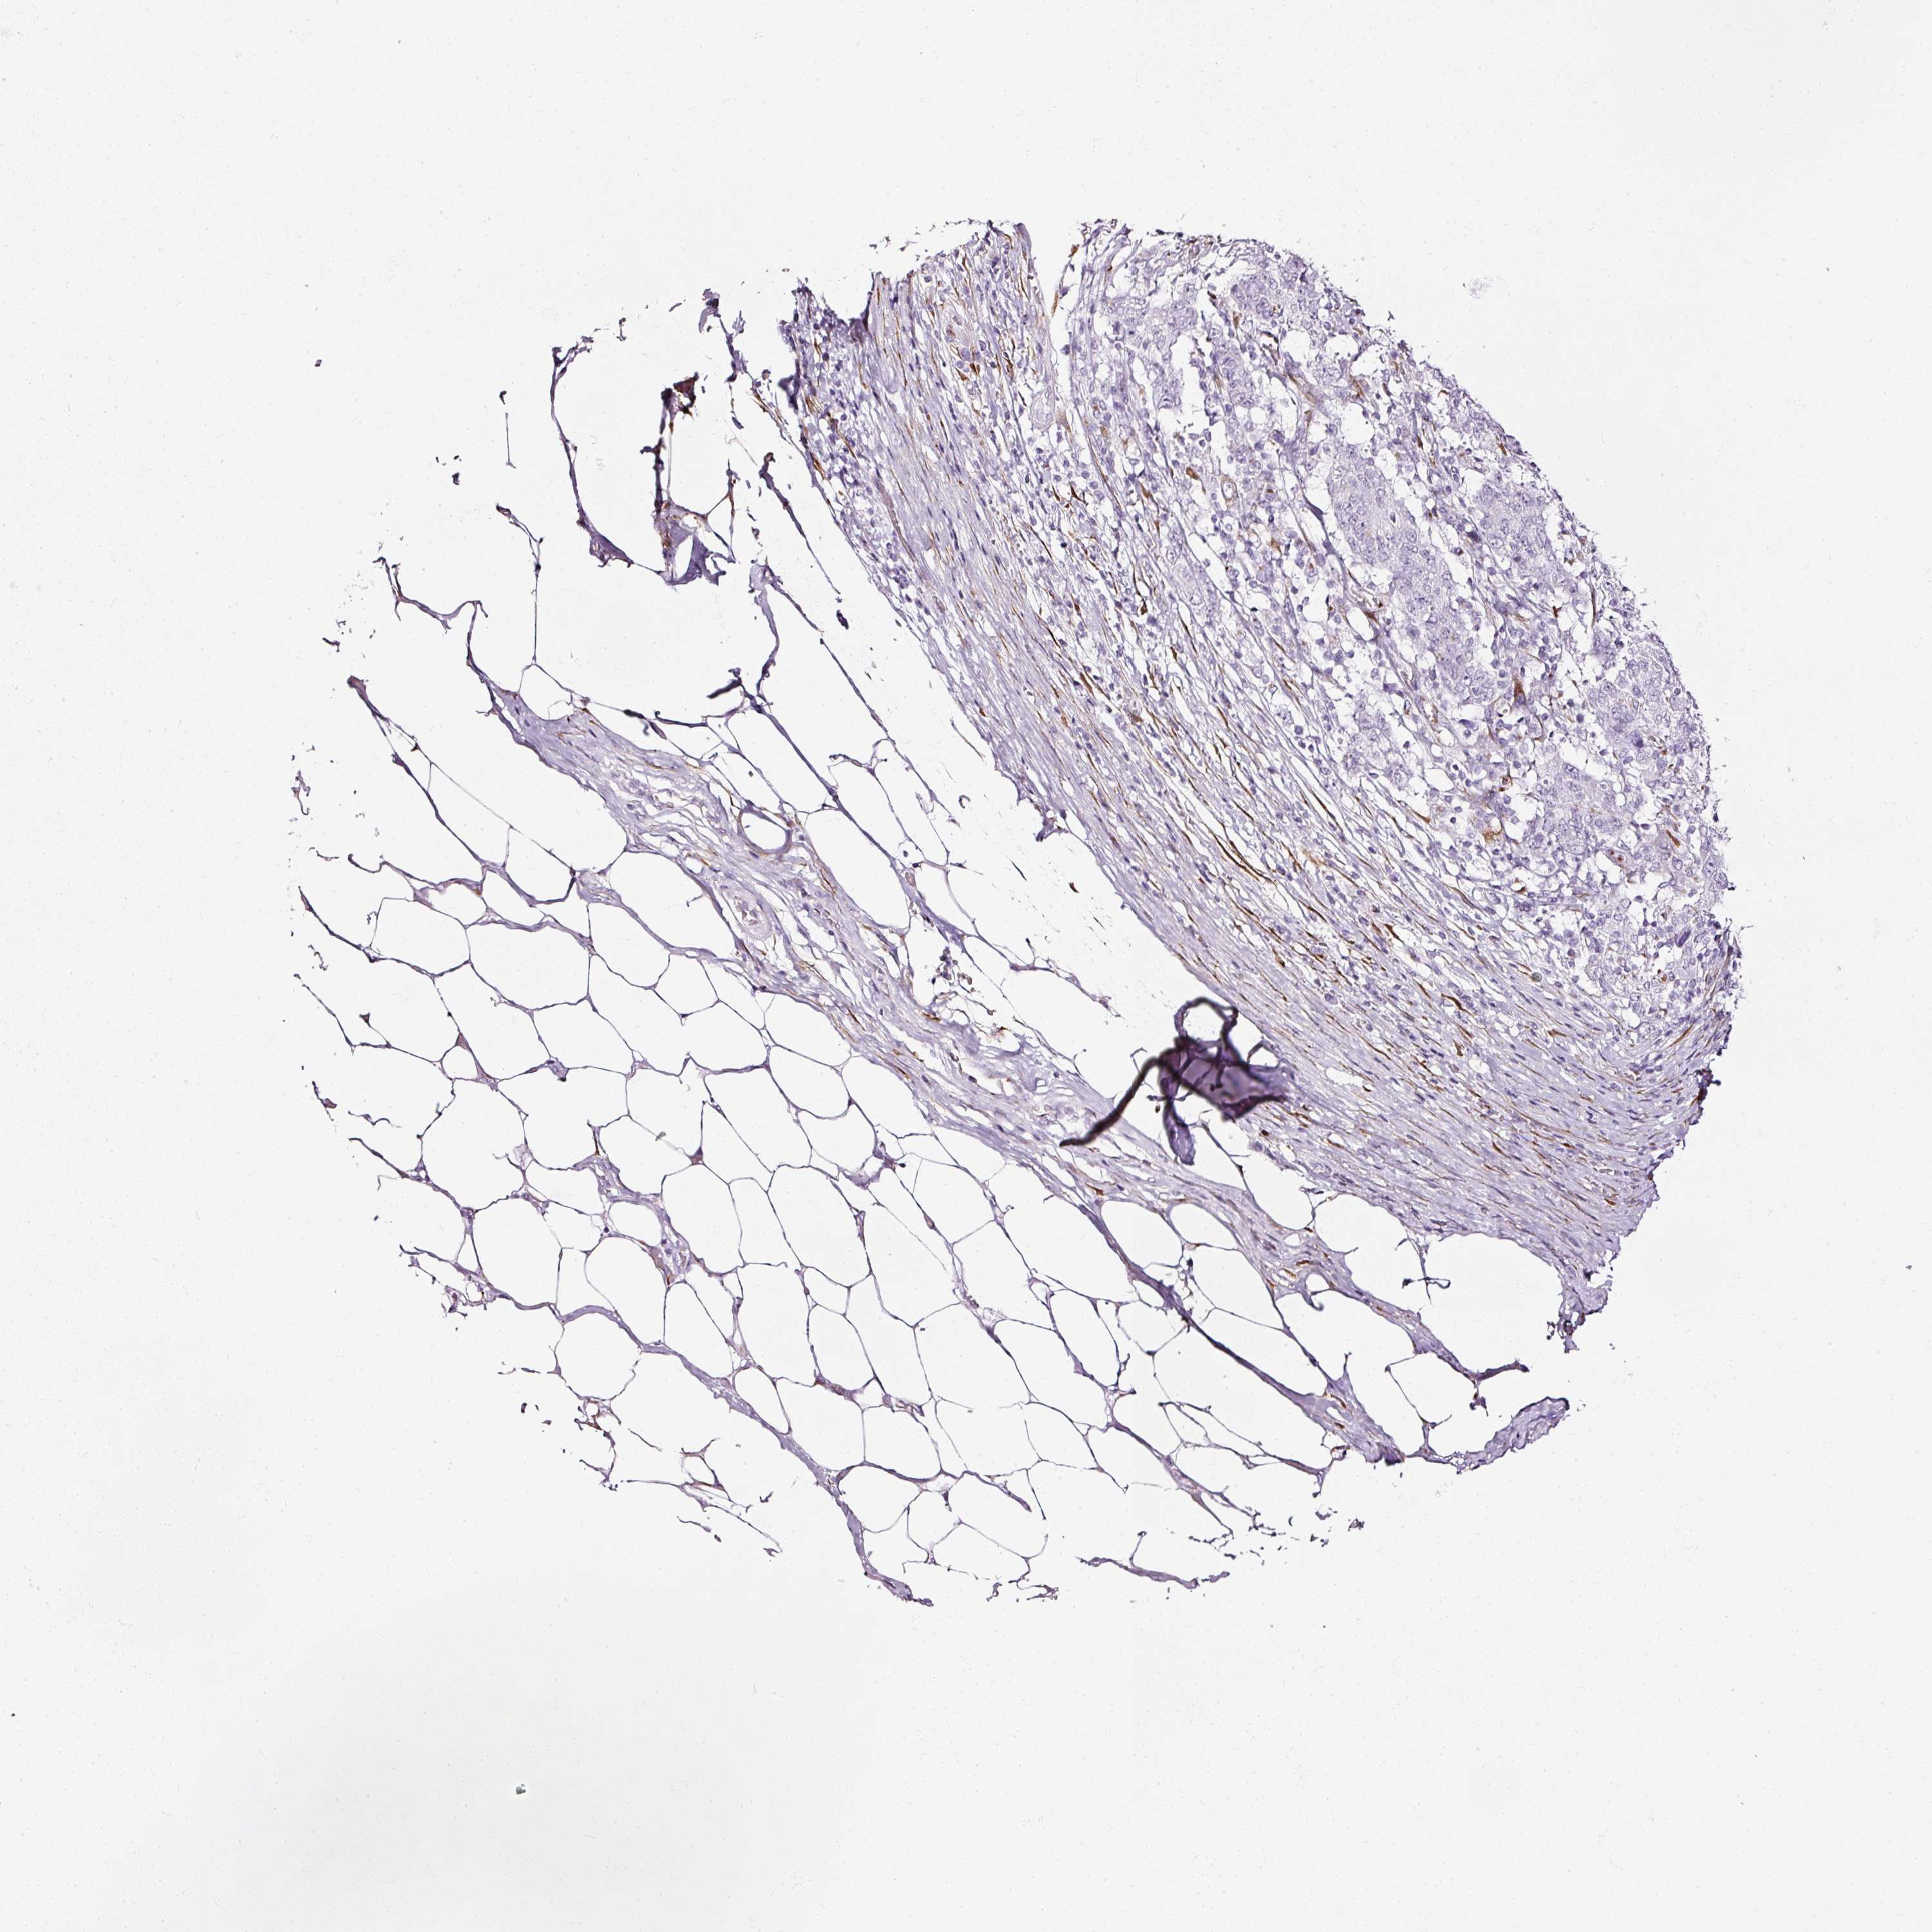

STOMACH CANCER - Protein expressioni

A mouse-over function shows sample information and annotation data. Click on an image to view it in a full screen mode. Samples can be filtered based on level of antibody staining by selecting one or several of the following categories: high, medium, low and not detected. The assay and annotation is described here.

Note that samples used for immunohistochemistry by the Human Protein Atlas do not correspond to samples in the TCGA dataset.

Antibody stainingi

Antibody staining in the annotated cell types in the current human tissue is reported as not detected, low, medium, or high, based on conventional immunohistochemistry profiling in selected tissues. This score is based on the combination of the staining intensity and fraction of stained cells.

Each image is clickable and will lead to virtual microscopy that enables deeper exploration of all samples and also displays staining intensity scores, fraction scores and subcellular localization as well as patient and tissue information for each sample.

Antibody HPA011249

Antibody CAB015227

Staining

High

Medium

Low

Not detected

Intensity

Strong

Moderate

Weak

Negative

Quantity

>75%

75%-25%

<25%

None

Location

Nuclear

Cytoplasmic/membranous

Cytoplasmic/membranous,nuclear

Adenocarcinoma, NOS